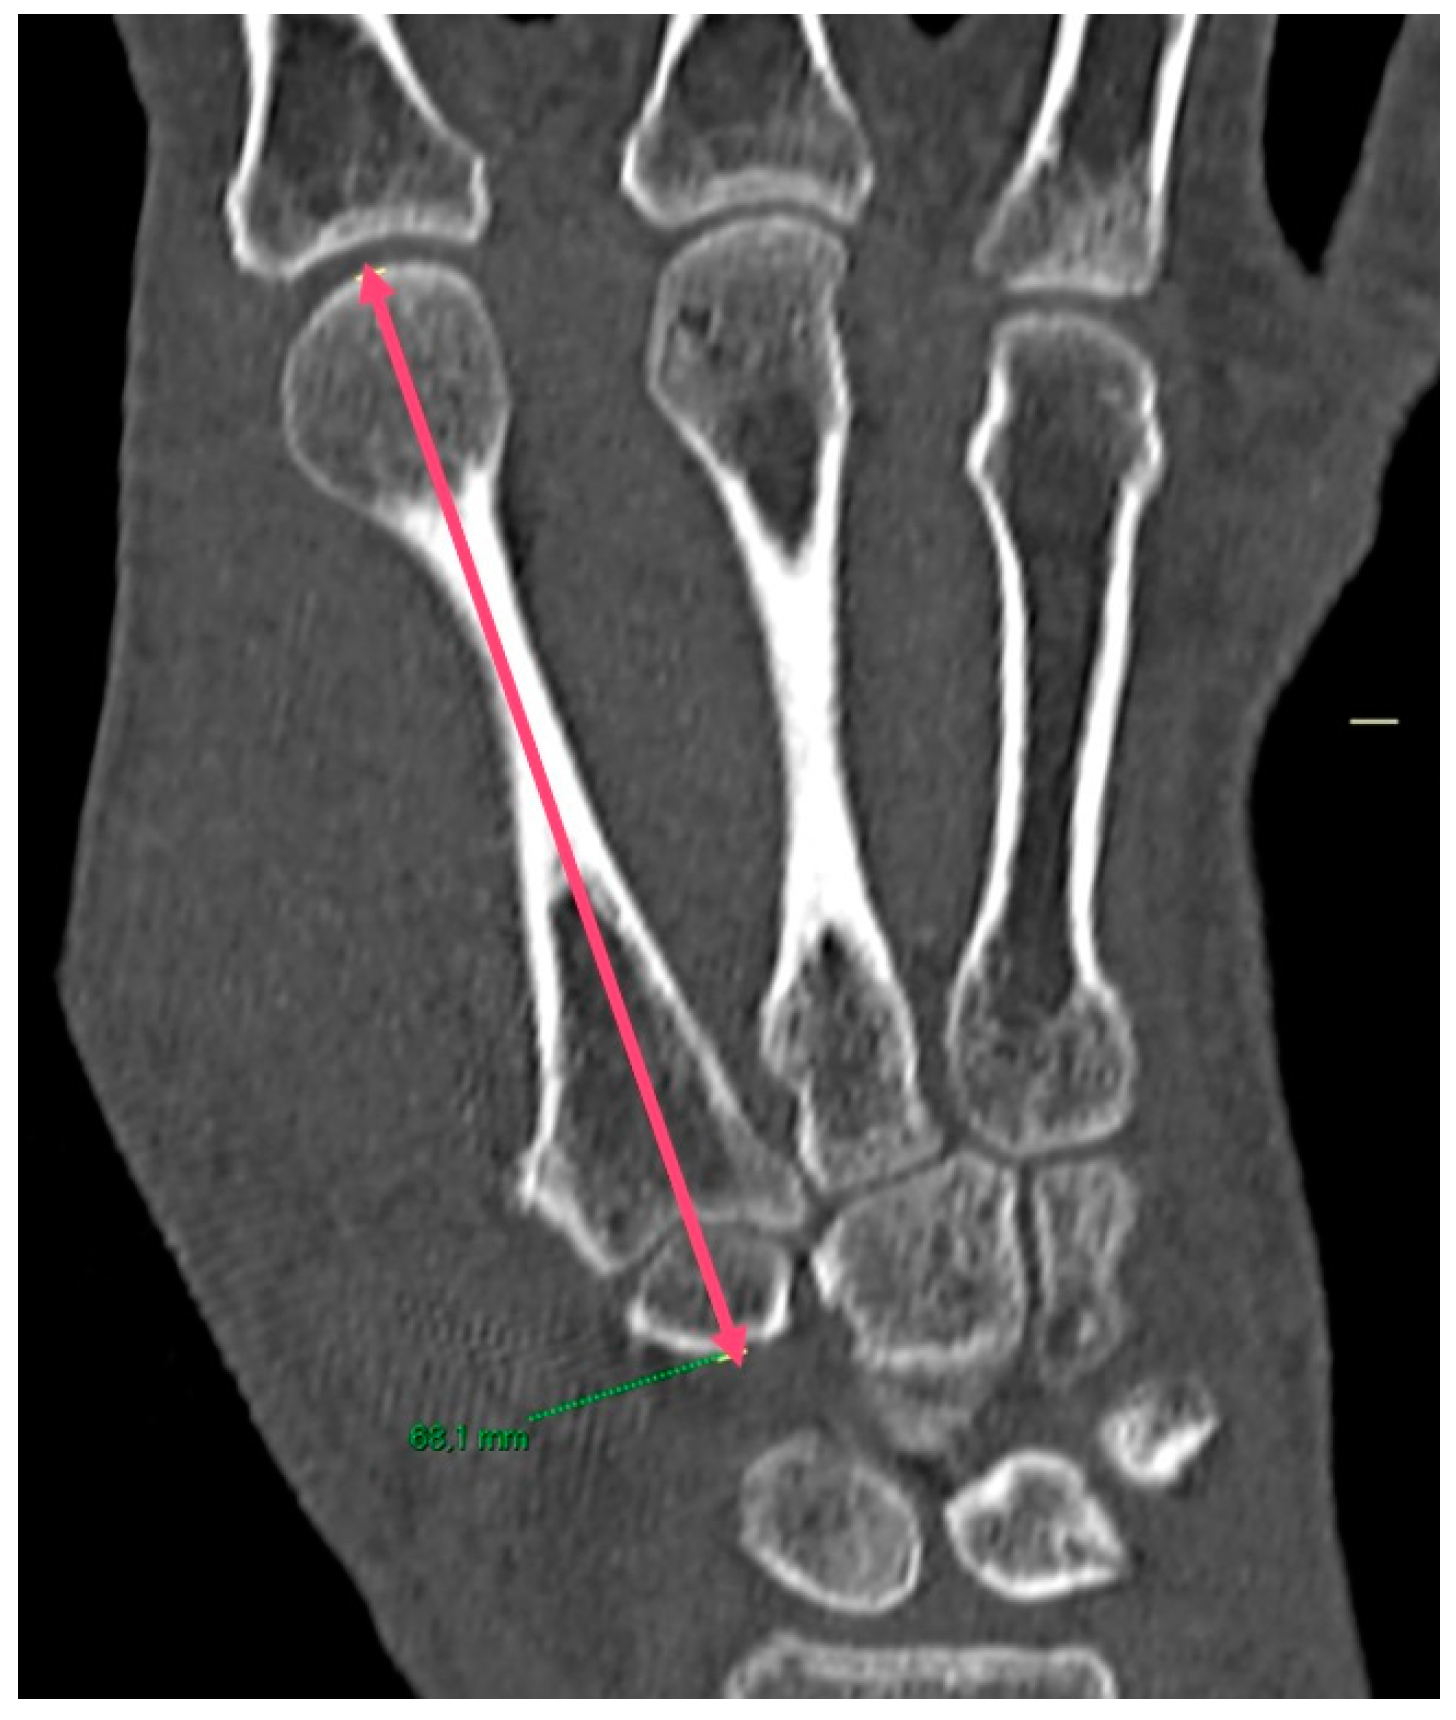

2.5. Imaging Analysis

3.1. CT Results

| PreOP M1 height | 54.9 mm | ±4.5 mm |

| PostOP M1 height | 57.9 mm | ±3.9 mm |

| PostOP M2 height | 74.0 mm | ±5.2 mm |

| PreOP M1-M2 ratio | 0.74 | 0.06 |

| PostOP M1-M2 ratio | 0.78 | 0.02 |

| Difference between Pre and PostOP M1-M2 ratio | 0.04 | 0.04 |

| M1 height difference PreOP and PostOP | 2.9 mm | ±3.2 mm |